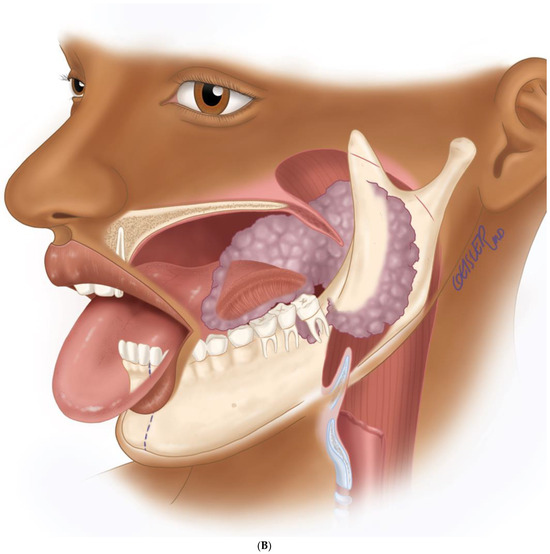

Figure 1.

Intraoral mass extending from the left posterior mandible and completely obliterating the airway.

The aim of this article is to describe the case of a 30-year-old African American female patient who presented at the Emergency Department (ED) in May 2023 at the University of Texas Medical Branch. As per the institution’s policy, IRB approval is not required for case reports, and photographic and informed consent was obtained from the patient to publish her case in a scientific journal, with progressive dyspnea, dysphagia, difficulty managed oral secretions, and decreased oral intake for the last three weeks. The family reported that she had increased swelling for the previous month, which was thought to be an odontogenic infection. The patient was seen by another ED-provider five weeks before and was discharged home with Amoxicillin-Clavulanic acid 875 mg PO every 12 h for 7 days. Oral and Maxillofacial Surgery services were consulted for urgent evaluation. Upon examination, the patient had a large expansile ulcerative mass intraorally, extending from the left posterior mandible and completely obliterating the oropharynx (Figure 1). The patient could not lay flat and was on 4 L of Oxygen via a nasal cannula. The patient denied any medical problems, taking any medications, or any allergy to any medicines. Based on the initial examination, the decision was to proceed with an awake tracheostomy to secure the airway, direct laryngoscopy, and incisional biopsy of the mass to establish the diagnosis. The procedure was performed uneventfully, and the patient had a CT Maxillofacial and Neck with an IV contrast. The scan showed a massive, expansile mass originating from the left posterior mandibular body, invading the pharynx’s posterior wall, with a complete obliteration of the oropharynx (Figure 2). Also, there was a highly suspicious enlarged lymph node at level 1B (Figure 3).

(A) Virtual surgical planning for the resection and reconstruction. The mass was exerting pressure on the occlusion, and the patient occlusion had to be readjusted. (B) Illustration showing the extent of the mass to the tongue, mandible, and oropharynx. Noted the dashed line for the planned hemi-mandibulectomy according to the VSP.